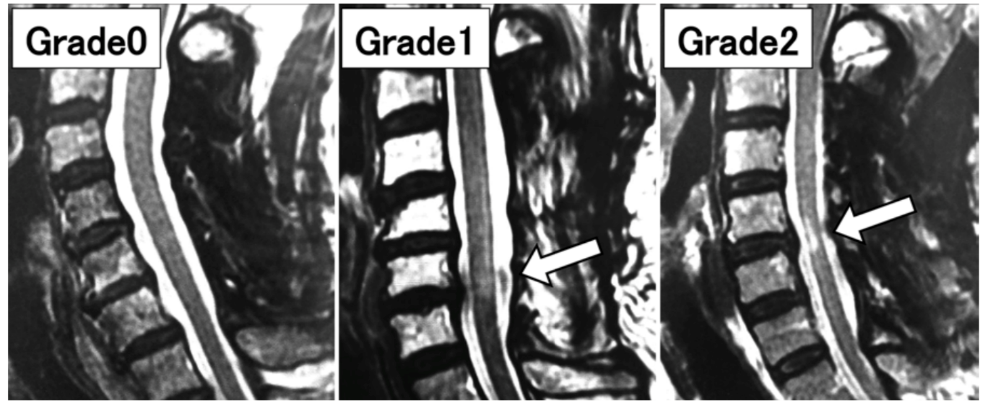

研究者总结,术后ISI反映无明显骨损伤的SCI患者术后症状严重程度和手术效果。48例(48%)患者术后观察到ISI变化,并与手术预后相关。